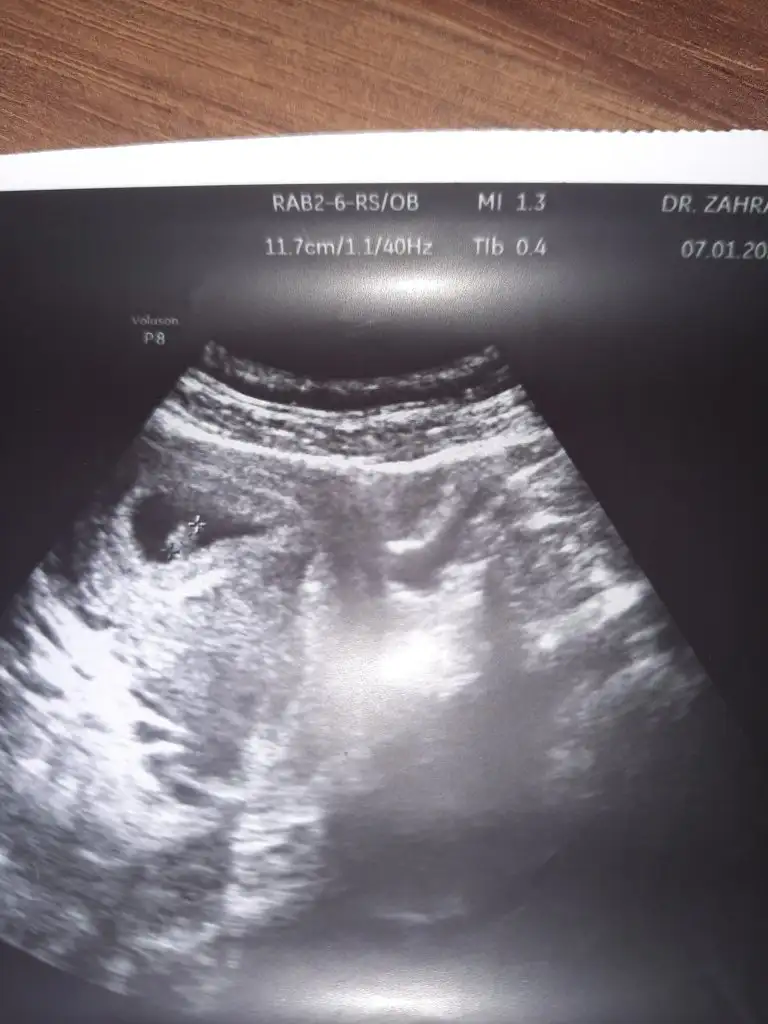

Daha çok küçük ama cinsiyetini çok merak ediyorum❤

Ilk bebişim cinsiyetin önemi yok tabiki ama ister istemez merak ediyorum banada tahminde bulunabilirmisiniz ❤ Çok erken ama keseden falan tahmin yapanlar oluyor diye paylaştım.